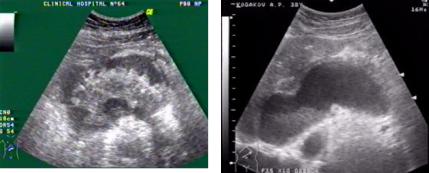

Ультразвуковая томография обнаруживает наличие жид-

костного образования, расположенного в проекции поджелудочной железы (рис.57).

Рис. 57. Ультразвуковые томограммы при хроническом панкреатите:

а - киста сальниковой сумки; б - формирующаяся киста поджелудочной железы